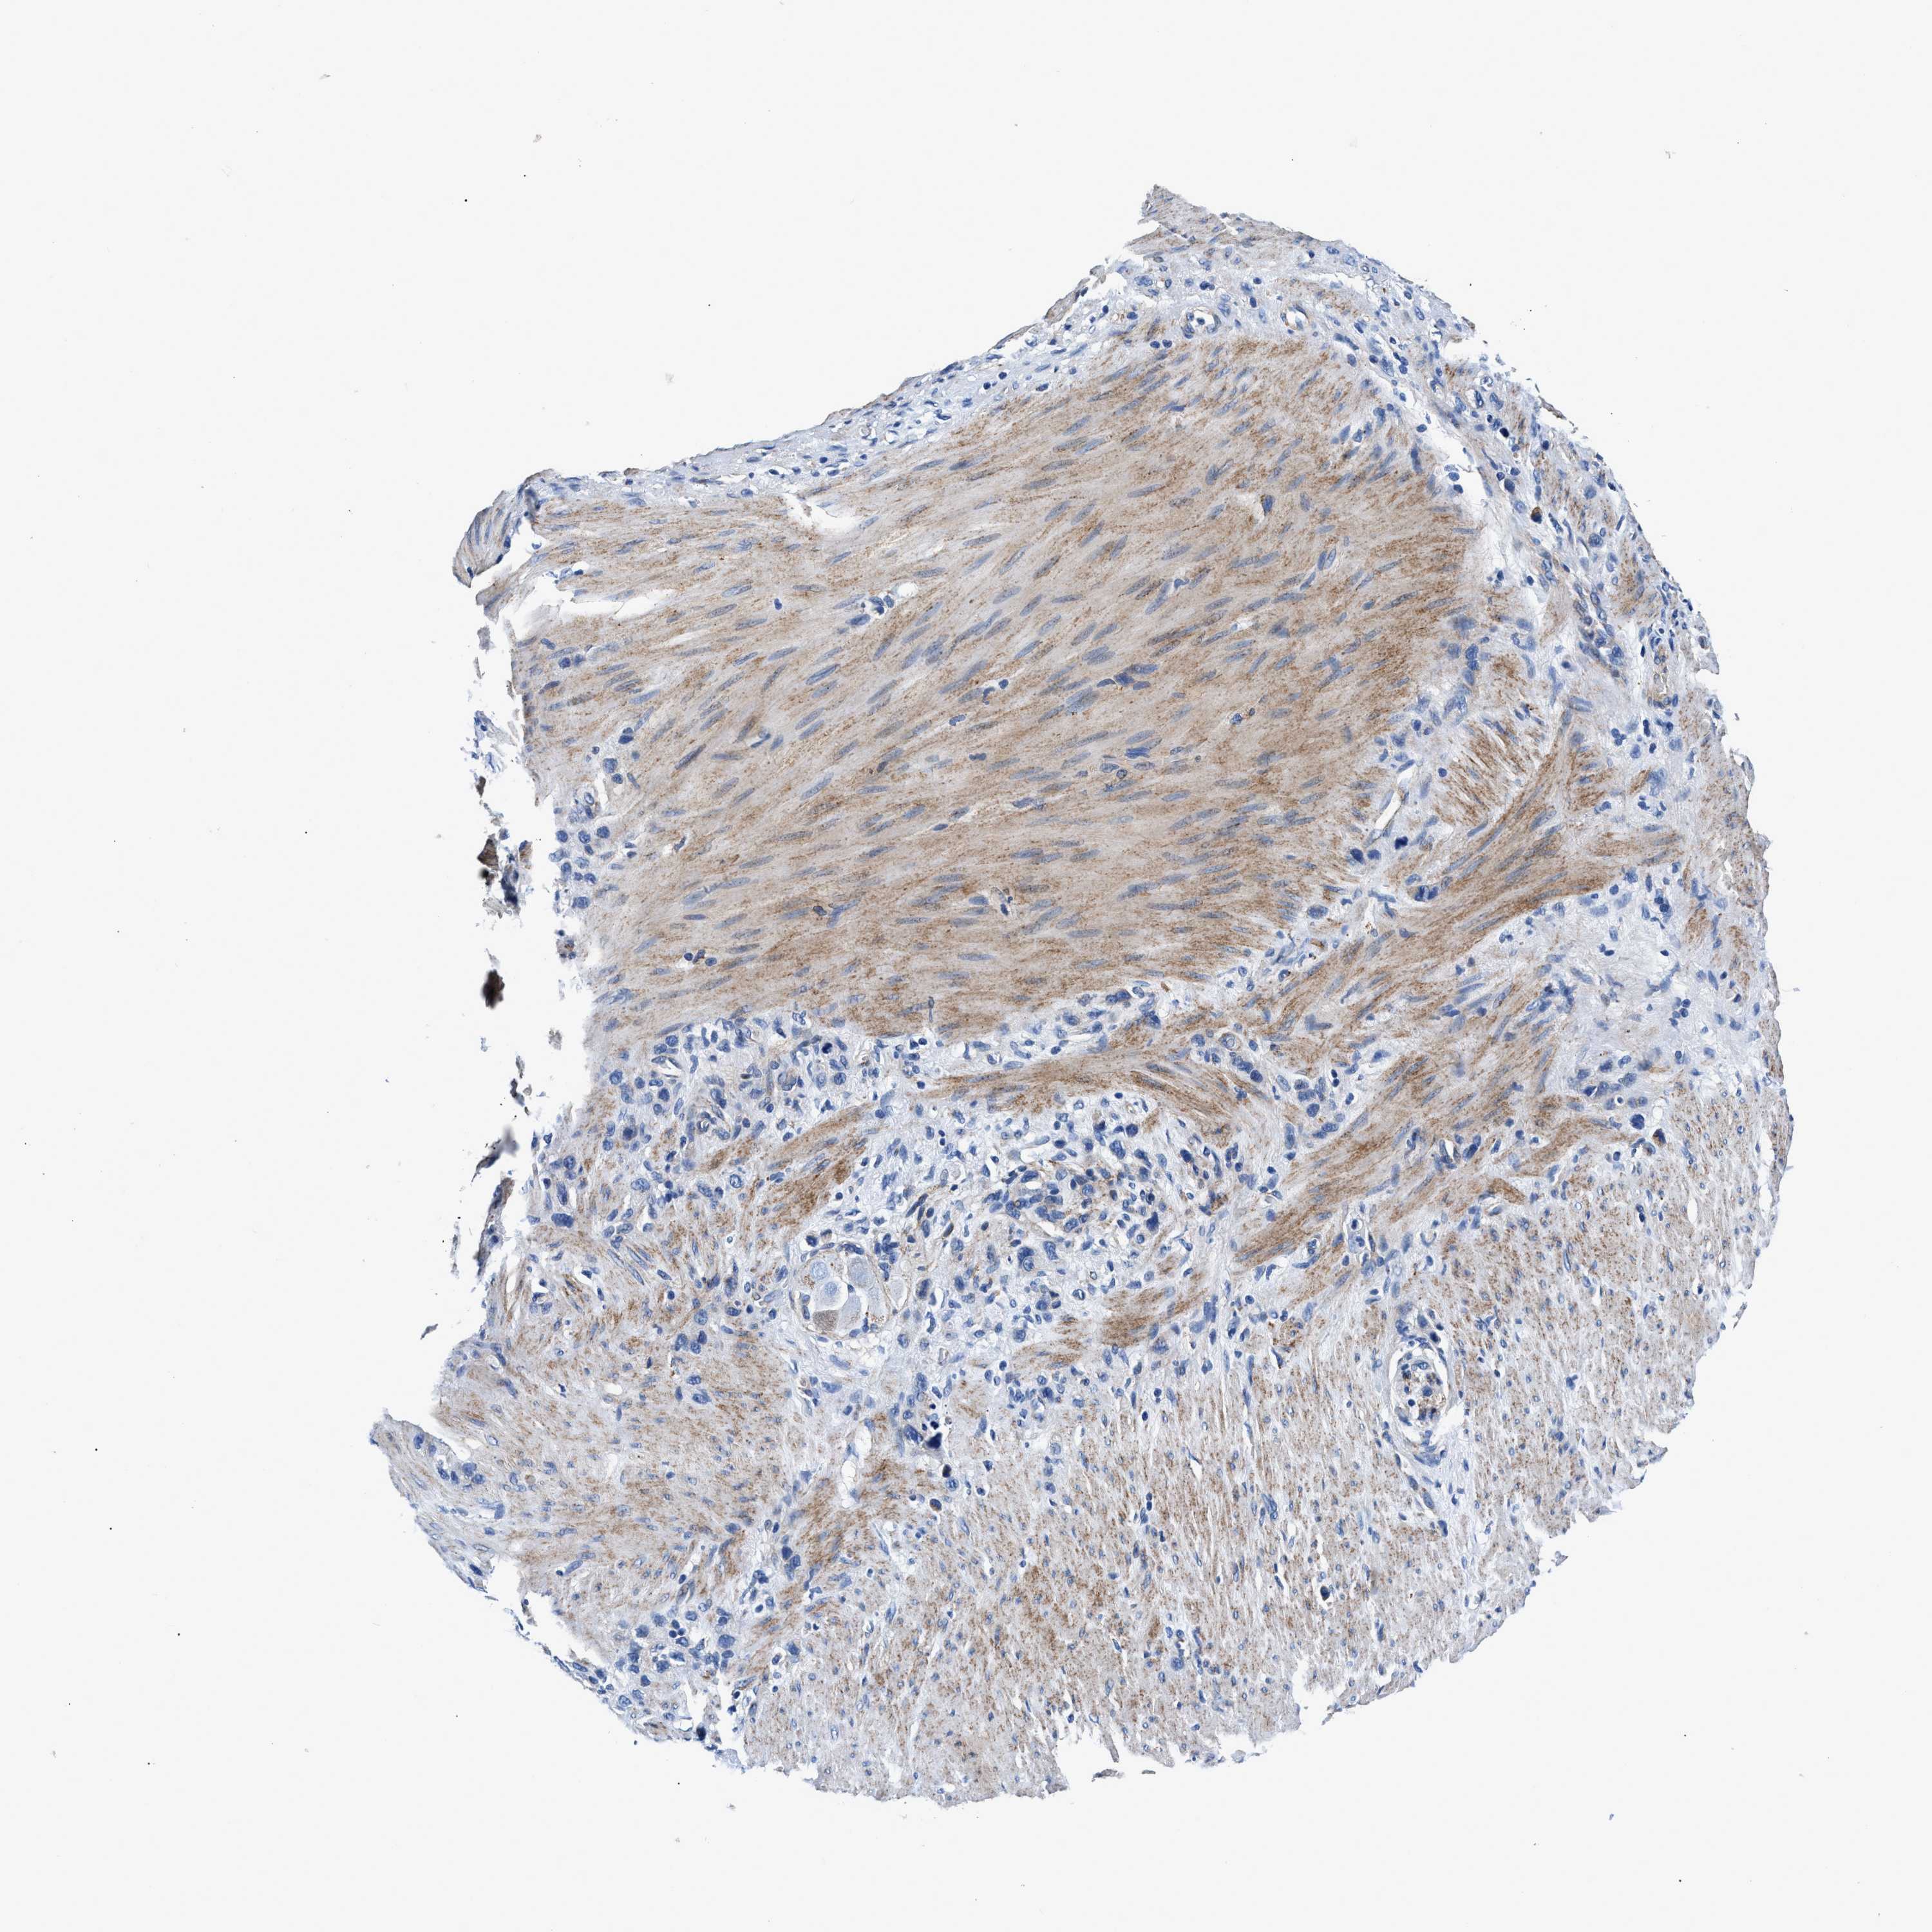

STOMACH CANCER - Protein expressioni

A mouse-over function shows sample information and annotation data. Click on an image to view it in a full screen mode. Samples can be filtered based on level of antibody staining by selecting one or several of the following categories: high, medium, low and not detected. The assay and annotation is described here.

Note that samples used for immunohistochemistry by the Human Protein Atlas do not correspond to samples in the TCGA dataset.

Antibody stainingi

Antibody staining in the annotated cell types in the current human tissue is reported as not detected, low, medium, or high, based on conventional immunohistochemistry profiling in selected tissues. This score is based on the combination of the staining intensity and fraction of stained cells.

Each image is clickable and will lead to virtual microscopy that enables deeper exploration of all samples and also displays staining intensity scores, fraction scores and subcellular localization as well as patient and tissue information for each sample.

Antibody CAB001960

Antibody CAB016353

Staining

High

Medium

Low

Not detected

Intensity

Strong

Moderate

Weak

Negative

Quantity

>75%

75%-25%

<25%

None

Location

Nuclear

Cytoplasmic/membranous

Cytoplasmic/membranous,nuclear

Adenocarcinoma, NOS

Adenocarcinoma, High grade